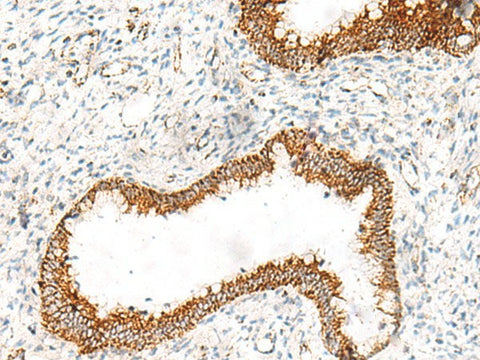

Applications IHC

IHC 1:40-1:200